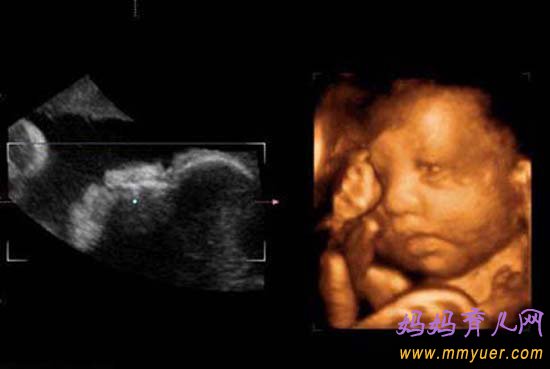

四维彩超多少钱?四维彩超,其实就是普通B超的升级版。从以前的黑白到如今的彩色,从以前的单一到现在的多功能。四维彩超不但效果比普通B超看得更加清楚,就连胎儿的眼睛、鼻子和嘴巴,也能看得一清二楚),而且更立体感。

四维彩超表面成像用于产科检查,不仅可观察到胎儿成长的过程,而且能够直观地看到胎儿在母体内的活动状况,如:呼吸情况,运动情况,包括整个身体大的运动,肢体的运动,甚至是胎儿细小的吞咽动作等。医生还可以通过四维彩超来观察胎儿的张力是否良好。

正是由于四维彩超是立体显示的,可以照到胎儿的各器官的发育状况,甚至可以观察到胎儿在母体里的状态,对胎儿畸形(如唇裂、腭裂、骨骼发育异常、心血管畸形等)能早期诊断,这也和以前的B超设备大不相同。

四维彩超什么时候做最好?一般来说,怀孕24-28周是照四维彩超的最佳时间,因为胎儿24周左右正是大脑突飞猛进的发育时期,这个时期的胎儿结构已经形成,胎儿的大小以及羊水适中,在宫内的活动空间较大,胎儿骨骼回声影响比较小,图像也比较清晰。

四维超声在三维超声的基础上有了实时动态的效果,准爸爸、准妈妈可以通过屏幕亲眼目睹宝宝在妈妈肚子里运动、呼吸、吞咽、打哈欠、伸舌头等生理活动,非常直观。